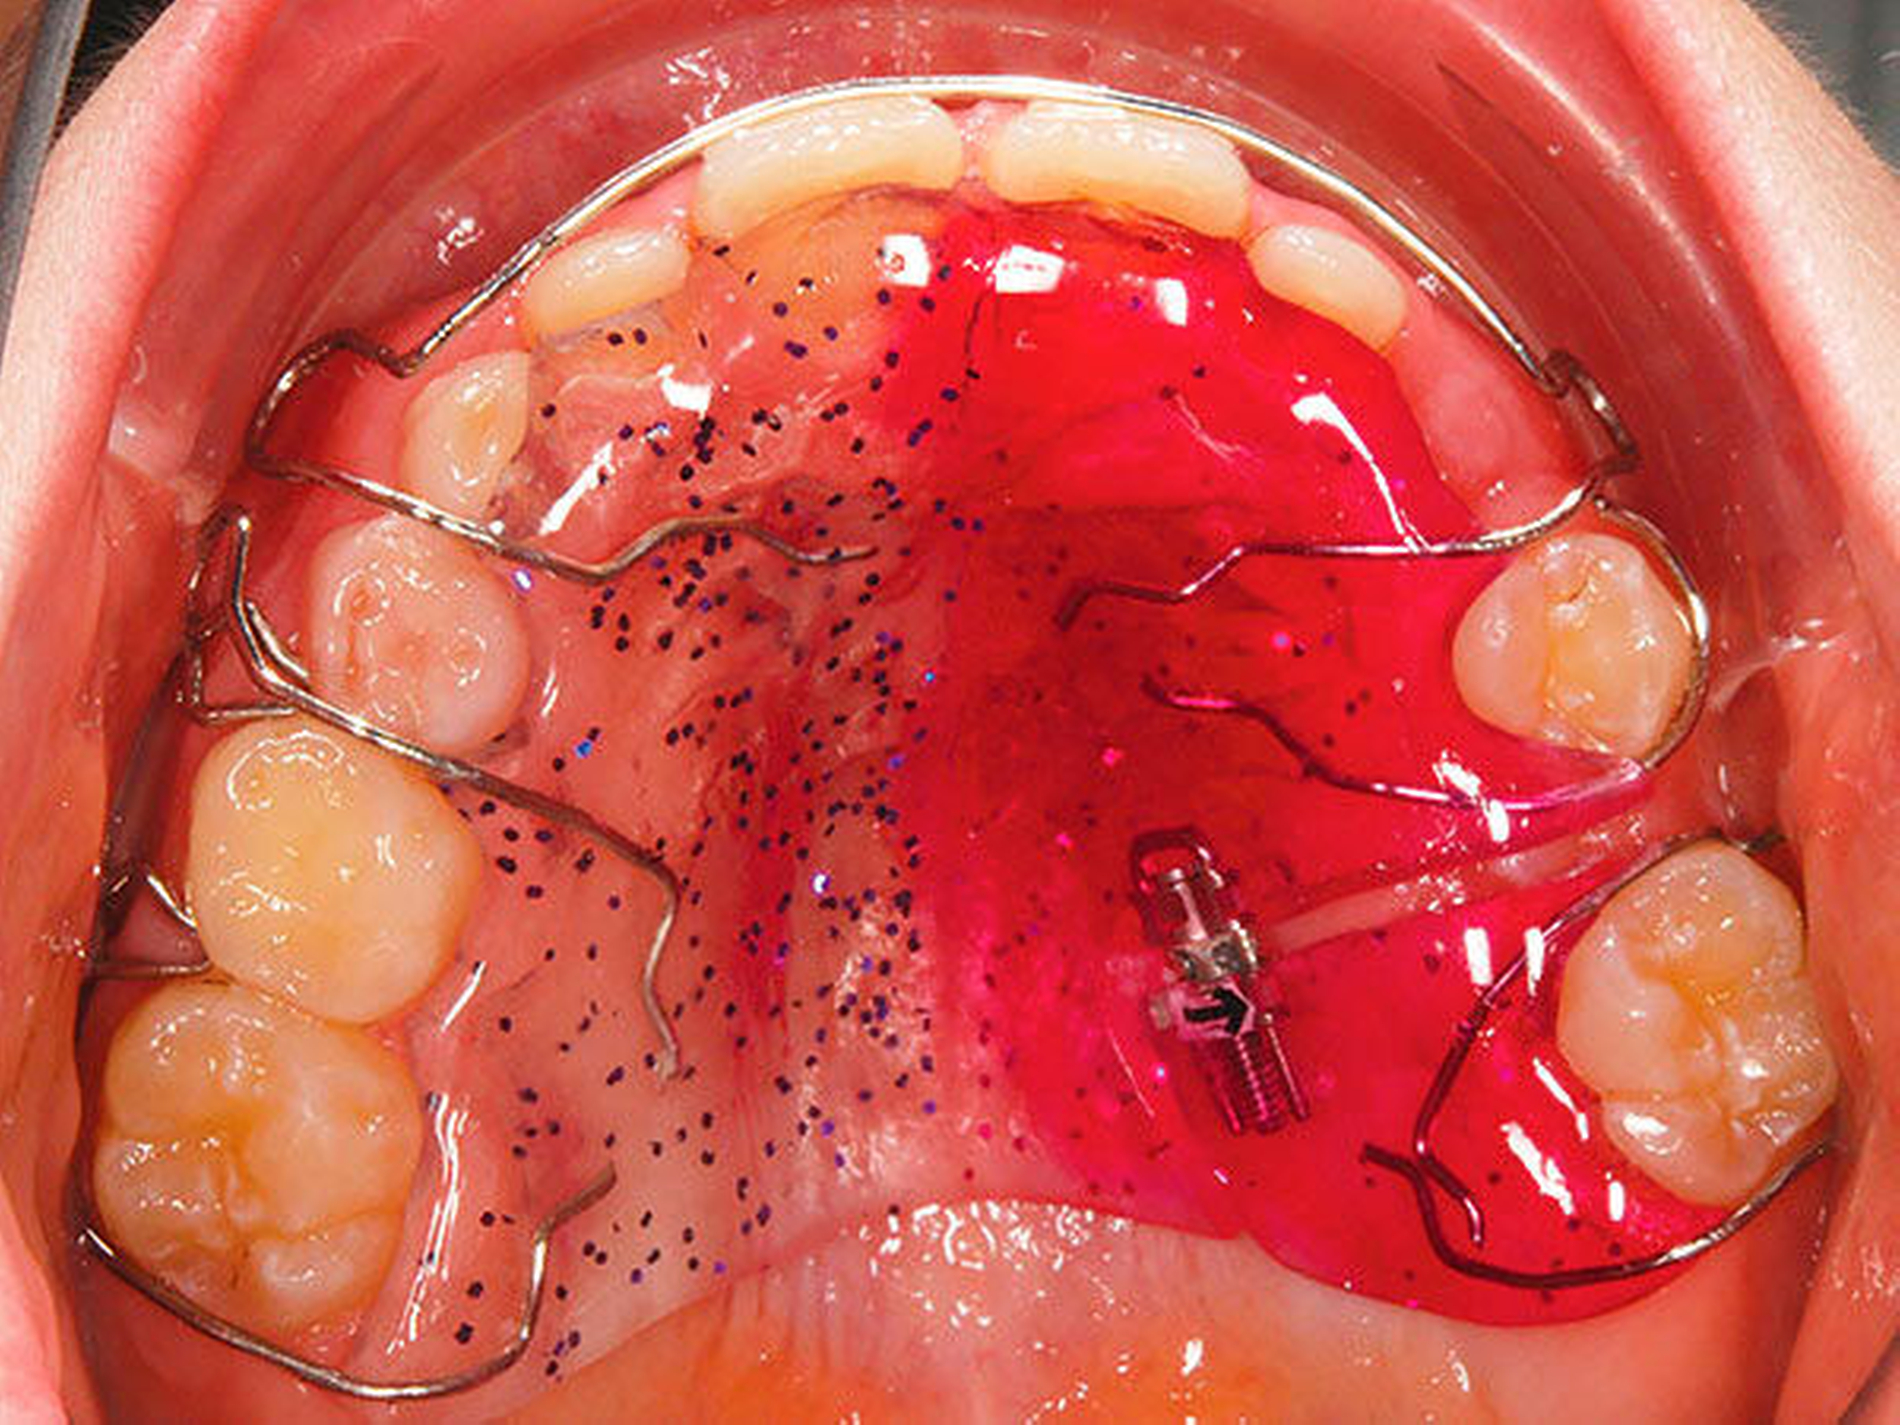

Besonders wichtig ist aus zahnärztlich-kieferorthopädischer Sicht die Beurteilung der lateralen Okklusionsverhältnisse [Kahl-Nieke, 2015]. Der unilaterale Kreuzbiss kommt ungefähr viermal häufiger vor als der bilaterale [Schopf, 2003]. Bei 80 Prozent der Kinder mit einseitigem Kreuzbiss tritt eine funktionelle Unterkieferabweichung auf [Kurol, 1992] und die Unterkiefermitte verschiebt sich dabei zur Kreuzbissseite [Santos Pinto, 2001] bei gleichzeitig asymmetrischer Kondylenposition. Diese reflektorische Einnahme der Kreuzbissstellung vergrößert die Anzahl der Okklusionskontakte, mit der Gefahr, dass nach kurzer Zeit diese transversale Fehlstellung des Unterkiefers neuromuskulär fixiert wird. Bei Belassen des Kreuzbisses kann eine skelettale Manifestation der Asymmetrie und eine dauerhafte Abweichung der Kinnmitte von der Gesichtsmitte resultieren [Hesse, 1997; O`byrn, 1995]. Erfolgt keine frühzeitige Therapie, besteht zudem die Gefahr einer Wachstumshemmung im Bereich der im Kreuzbiss „eingefangenen“ Oberkieferseite. Eine kieferorthopädische Frühbehandlung scheint präventiv gegen eine skelettale Adaptation und gegen eine Persistenz des Kreuzbisses in die permanente Dentition zu wirken [Harrison, 2001]. Das Überstellen des lateralen Kreuzbisses durch transversale Weitung des Oberkiefers kann beispielsweise mittels forcierter Gaumennahterweiterung [Köbel, 2017] erfolgen und wirkt sich neben einer Verbesserung der respiratorischen Situation günstig auf die Beseitigung skelettaler und dentoalveolärer Asymmetrien aus [Hesse, 1997; Santos Pinto, 2001] (Abbildung 3).